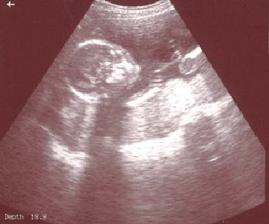

12.5. Tak jsem vážně Gagarin 😀 Byl jsem s mamuškou a taťuldou na velkym UTZ a první co ze mě bylo vidět byl - bimbásek 😀 takže je to jasný 😀 pan dochtor Čutka na genetice byl strašně srandovní, pořád mě honil přes bříško takovou věcičkou a maminku rozptyloval divnejma otázkama - ale byl moc milej 😉 a pochválil mě, že mám průměrnej mozeček, obě ledviny a že se mi chce čůrat 🙂